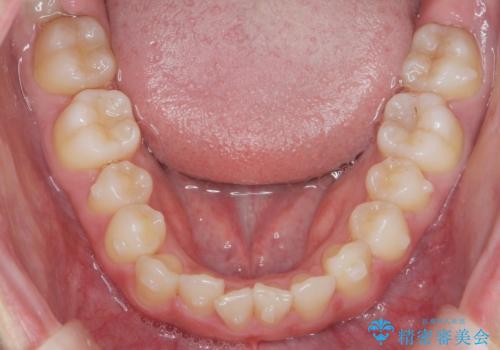

ガタつきの改善 マウスピース矯正治療

- 歯のがたつきの改善を求めて、矯正治療を希望され来院されました。

少量の歯のディスキング、歯列弓拡大、アタッチメントを装着することで審美的な歯列へとマウスピース矯正インビザラインを用いて治療を行います。

マウスピース矯正は装着時間の遵守が非常に大切ですが、しっかりと20時間/日以上の装着を守っていただいたおかげで良好な治療結果を得ることができました。